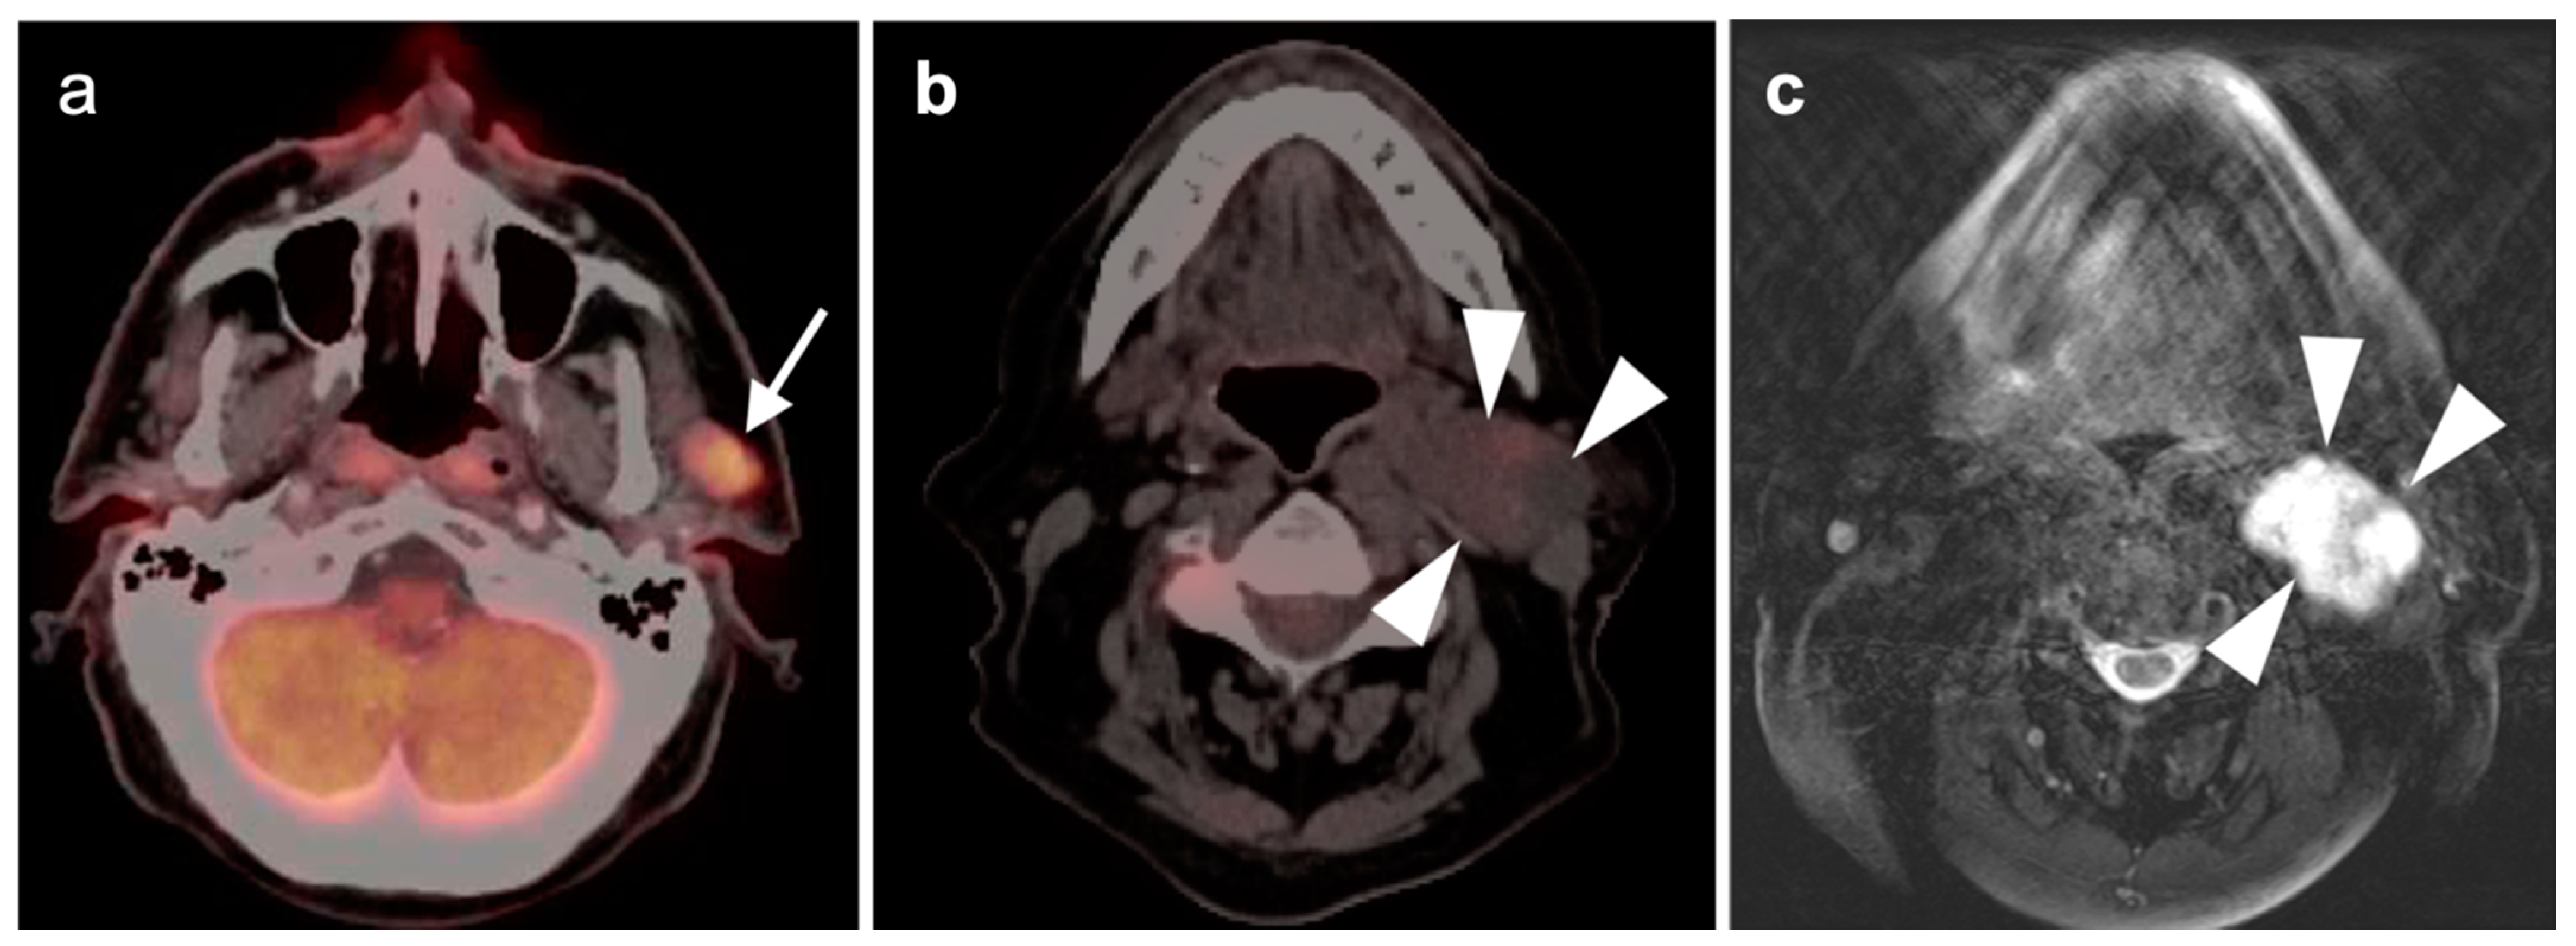

2.5. Major and Minor Salivary Gland, Lacrimal Gland Tumors

- Warthin tumor

- Mucoepidermoid carcinoma

- Adenoid cystic carcinoma